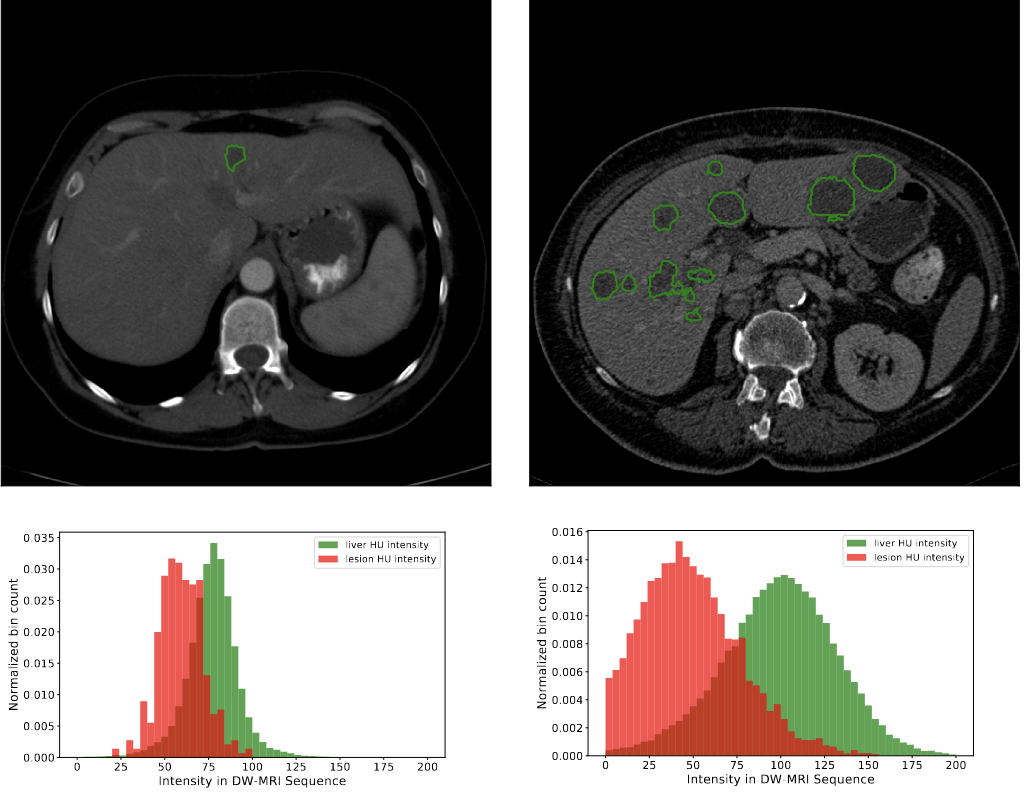

The liver tumor segmentation benchmark (lits)Patrick Bilic, Patrick Christ, Hongwei Bran Li, Eugene Vorontsov, Avi Ben-Cohen, Georgios Kaissis, Adi Szeskin, Colin Jacobs, Gabriel Efrain Humpire Mamani, Gabriel Chartrand, and othersMedical Image Analysis[ bibtex | html | abstract ]@article{bilic2023liver, title = {The liver tumor segmentation benchmark (lits)}, author = {Bilic, Patrick and Christ, Patrick and Li, Hongwei Bran and Vorontsov, Eugene and Ben-Cohen, Avi and Kaissis, Georgios and Szeskin, Adi and Jacobs, Colin and Mamani, Gabriel Efrain Humpire and Chartrand, Gabriel and others}, journal = {Medical Image Analysis}, volume = {84}, pages = {102680}, year = {2023}, publisher = {Elsevier}, abbr = {bilic2023liver.png}, html = {https://www.sciencedirect.com/science/article/pii/S1361841522003085} }In this work, we report the set-up and results of the Liver Tumor Segmentation Benchmark (LITS) organized in conjunction with the IEEE International Symposium on Biomedical Imaging (ISBI) 2016 and International Conference On Medical Image Computing Computer Assisted Intervention (MICCAI) 2017. Twenty four valid state-of-the-art liver and liver tumor segmentation algorithms were applied to a set of 131 computed tomography (CT) volumes with different types of tumor contrast levels (hyper-/hypo-intense), abnormalities in tissues (metastasectomie) size and varying amount of lesions. The submitted algorithms have been tested on 70 undisclosed volumes. The dataset is created in collaboration with seven hospitals and research institutions and manually reviewed by independent three radiologists. We found that not a single algorithm performed best for liver and tumors. The best liver segmentation algorithm achieved a Dice score of 0.96(MICCAI) whereas for tumor segmentation the best algorithm evaluated at 0.67(ISBI) and 0.70(MICCAI). The LITS image data and manual annotations continue to be publicly available through an online evaluation system as an ongoing benchmarking resource.

Automatic liver and tumor segmentation of CT and MRI volumes using cascaded fully convolutional neural networksPatrick Ferdinand Christ, Florian Ettlinger, Felix Grün, Mohamed Ezzeldin A Elshaera, Jana Lipkova, Sebastian Schlecht, Freba Ahmaddy, Sunil Tatavarty, Marc Bickel, Patrick Bilic, and othersarXiv preprint arXiv:1702.05970[ bibtex | html | abstract ]@article{christ2017automatic, title = {Automatic liver and tumor segmentation of CT and MRI volumes using cascaded fully convolutional neural networks}, author = {Christ, Patrick Ferdinand and Ettlinger, Florian and Gr{\"u}n, Felix and Elshaera, Mohamed Ezzeldin A and Lipkova, Jana and Schlecht, Sebastian and Ahmaddy, Freba and Tatavarty, Sunil and Bickel, Marc and Bilic, Patrick and others}, journal = {arXiv preprint arXiv:1702.05970}, year = {2017}, abbr = {christ2017automatic.png}, html = {https://arxiv.org/abs/1702.05970} }Automatic segmentation of the liver and hepatic lesions is an important step towards deriving quantitative biomarkers for accurate clinical diagnosis and computer-aided decision support systems. This paper presents a method to automatically segment liver and lesions in CT and MRI abdomen images using cascaded fully convolutional neural networks (CFCNs) enabling the segmentation of a large-scale medical trial or quantitative image analysis. We train and cascade two FCNs for a combined segmentation of the liver and its lesions. In the first step, we train a FCN to segment the liver as ROI input for a second FCN. The second FCN solely segments lesions within the predicted liver ROIs of step 1. CFCN models were trained on an abdominal CT dataset comprising 100 hepatic tumor volumes. Validations on further datasets show that CFCN-based semantic liver and lesion segmentation achieves Dice scores over 94% for liver with computation times below 100s per volume. We further experimentally demonstrate the robustness of the proposed method on an 38 MRI liver tumor volumes and the public 3DIRCAD dataset.

Automated unsupervised segmentation of liver lesions in ct scans via cahn-hilliard phase separationJana Lipková, Markus Rempfler, Patrick Christ, John Lowengrub, and Bjoern H MenzearXiv preprint arXiv:1704.02348[ bibtex | html | abstract ]@article{lipkova2017automated, title = {Automated unsupervised segmentation of liver lesions in ct scans via cahn-hilliard phase separation}, author = {Lipkov{\'a}, Jana and Rempfler, Markus and Christ, Patrick and Lowengrub, John and Menze, Bjoern H}, journal = {arXiv preprint arXiv:1704.02348}, year = {2017}, abbr = {lipkova2017automated.png}, html = {https://arxiv.org/pdf/1704.02348.pdf} }The segmentation of liver lesions is crucial for detection, di- agnosis and monitoring progression of liver cancer. However, design of accurate automated methods remains challenging due to high noise in CT scans, low contrast between liver and lesions, as well as large lesion variability. We propose a 3D automatic, unsupervised method for liver le- sions segmentation using a phase separation approach. It is assumed that liver is a mixture of two phases: healthy liver and lesions, represented by different image intensities polluted by noise. The Cahn-Hilliard equation is used to remove the noise and separate the mixture into two distinct phases with well-defined interfaces. This simplifies the lesion detection and segmentation task drastically and enables to segment liver lesions by thresholding the Cahn-Hilliard solution. The method was tested on 3Dircadb and LITS dataset.